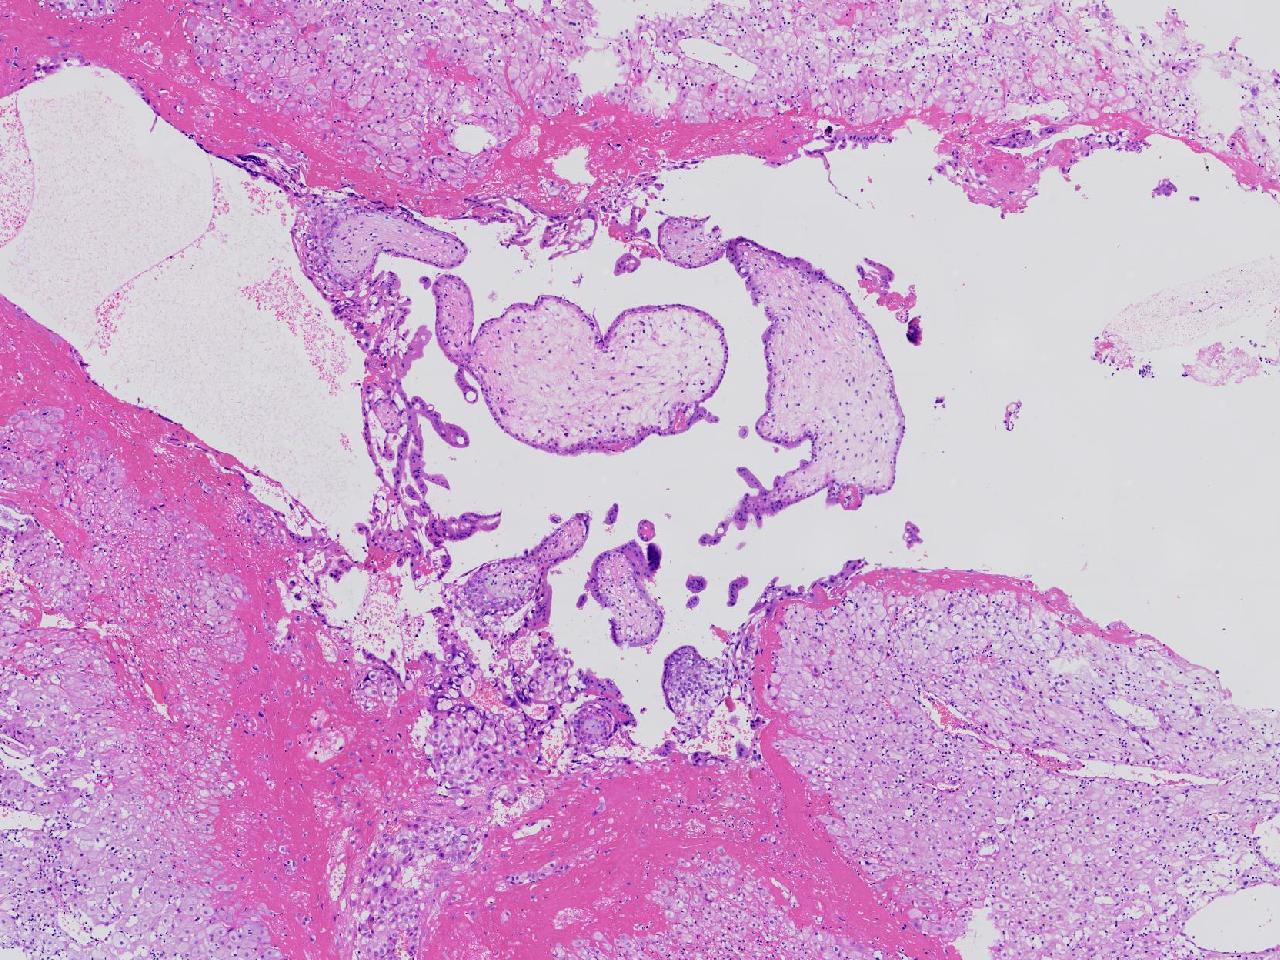

女,29岁,药物流产20余天,阴道少量出血20余天。行诊刮术。

宫腔内容物

灰粉色不整形软组织多块,4X3X3厘米,部分为血凝块。

送检组织为胎盘绒毛及蜕膜组织及滋养层细胞考虑为不全流产